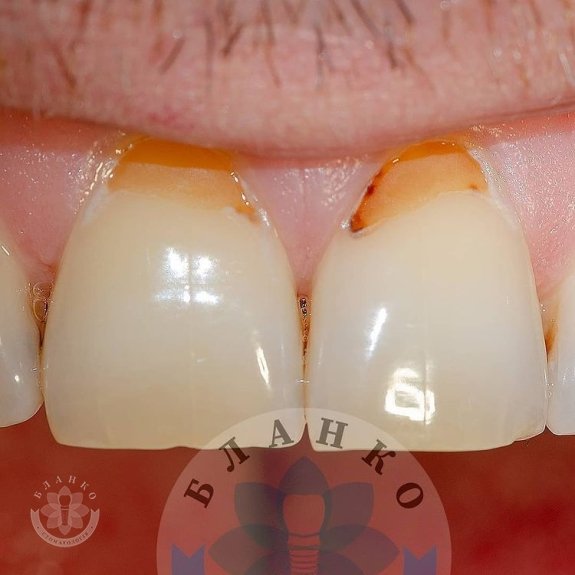

Карієс центральних різців верхньої щелепи.

💎1 фото – вихідна ситуація пацієнта.